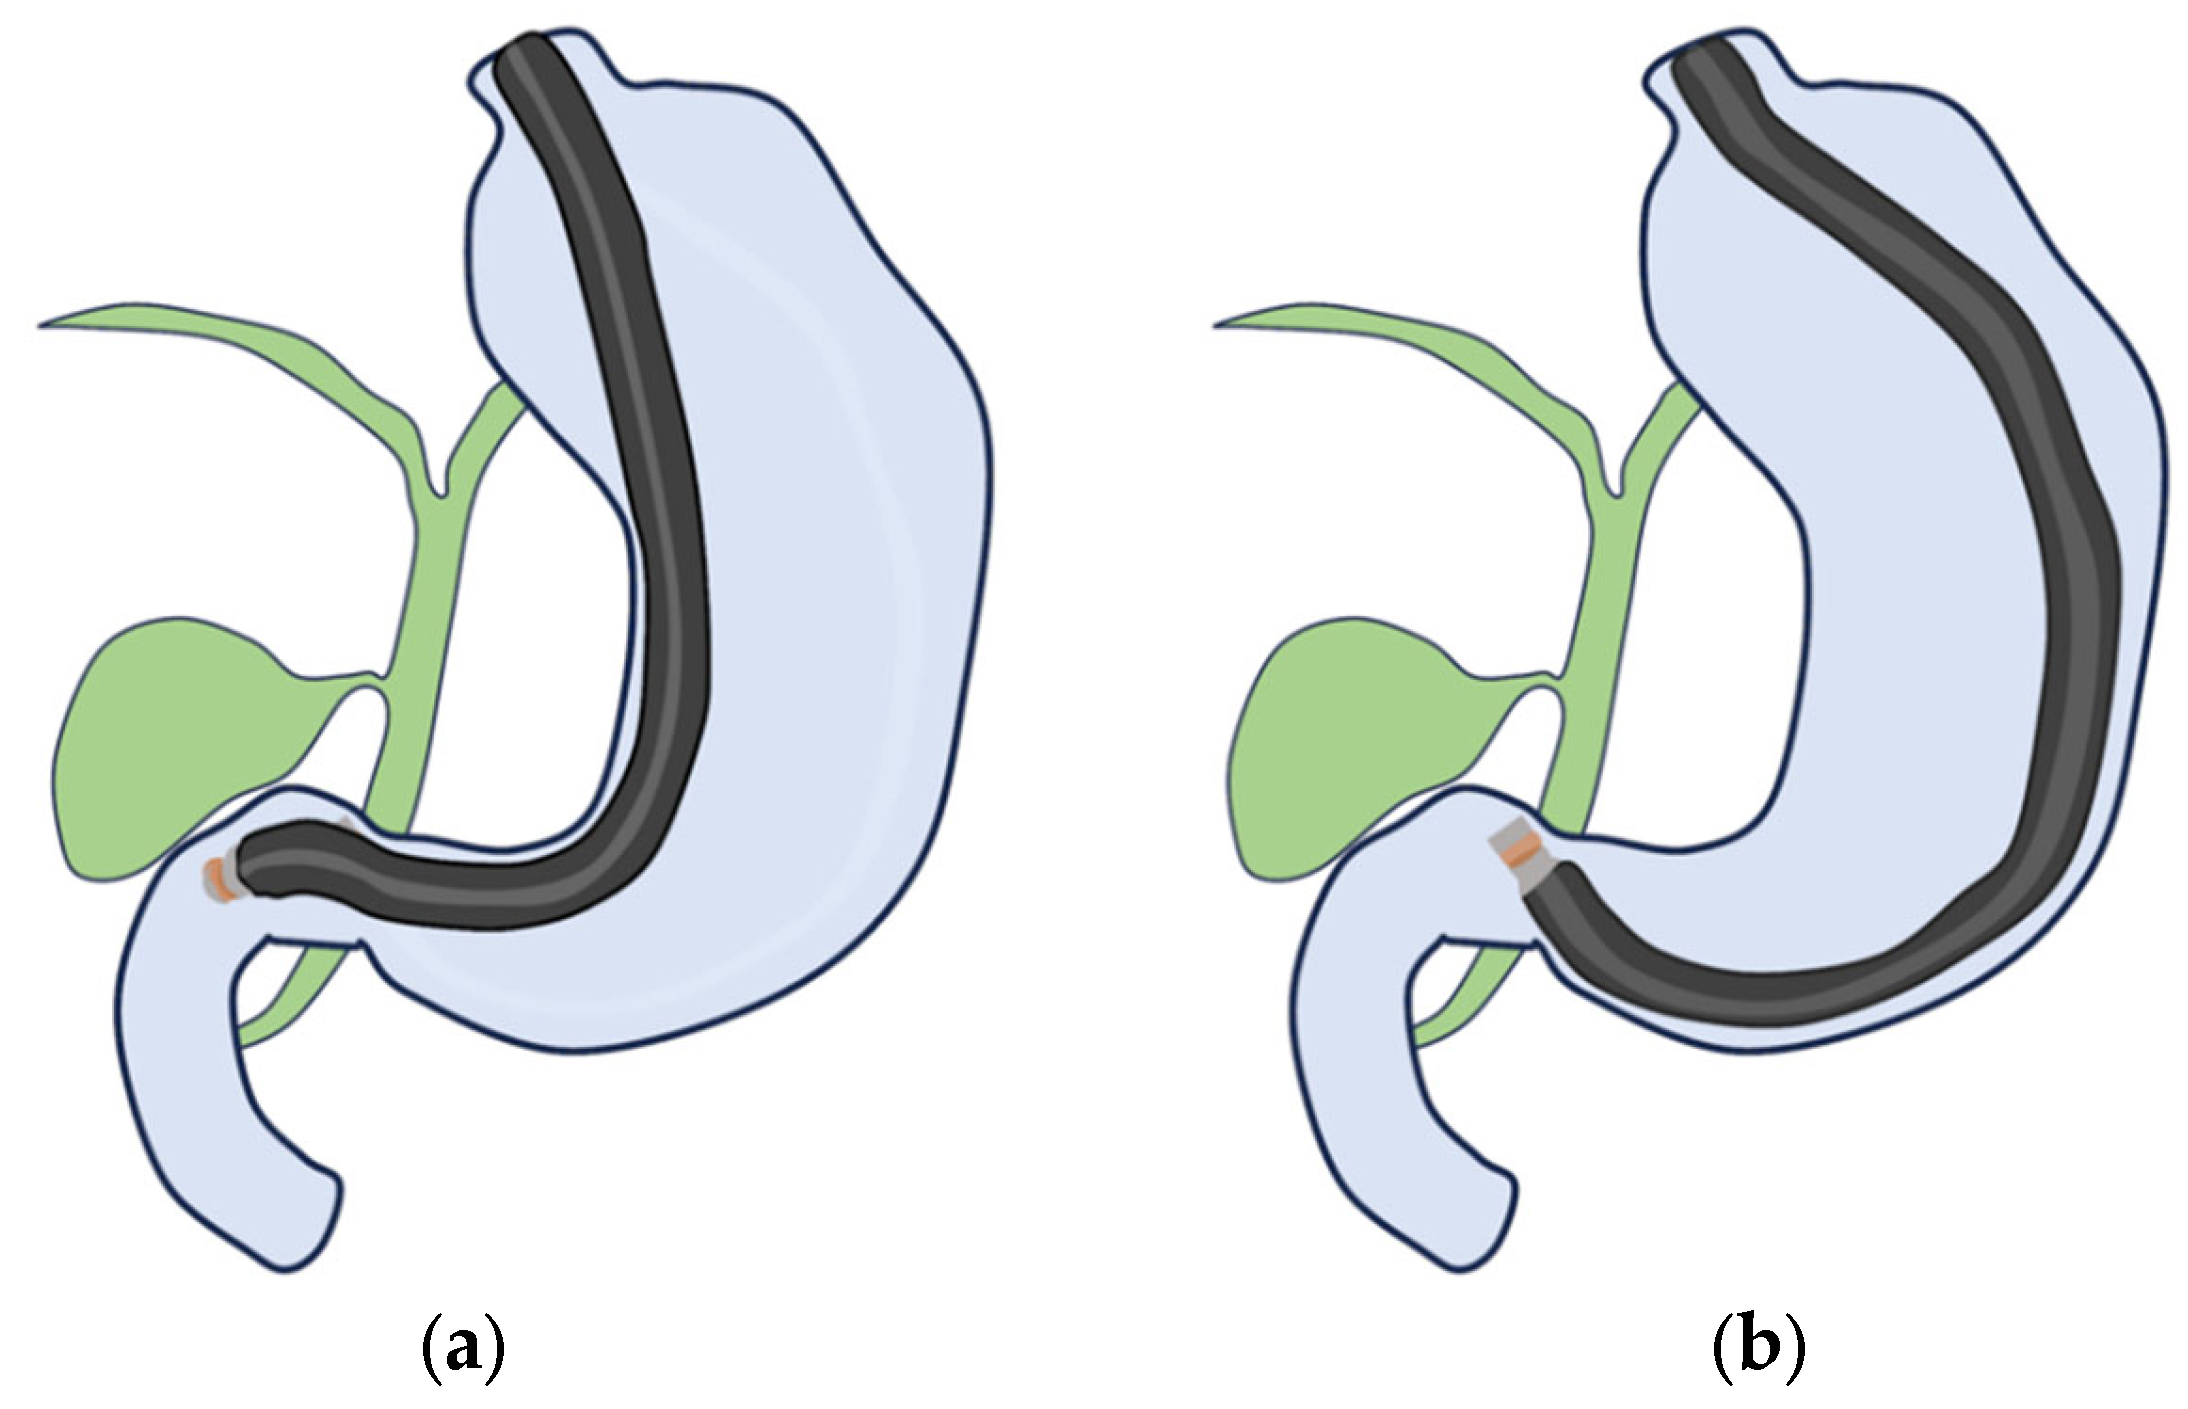

4. EUS Scope

- (i)

- RS-EUS

- (ii)

- CL-EUS

- Kaneko, M.; Katanuma, A.; Maguchi, H.; Takahashi, K.; Osanai, M.; Yane, K.; Hashigo, S.; Harada, R.; Kato, S.; Kato, R.; et al. Prospective, randomized, comparative study of delineation capability of radial scanning and curved linear array endoscopic ultrasound for the pancreaticobiliary region. Endosc. Int. Open 2014, 2, E160–E170. [Google Scholar] [CrossRef]